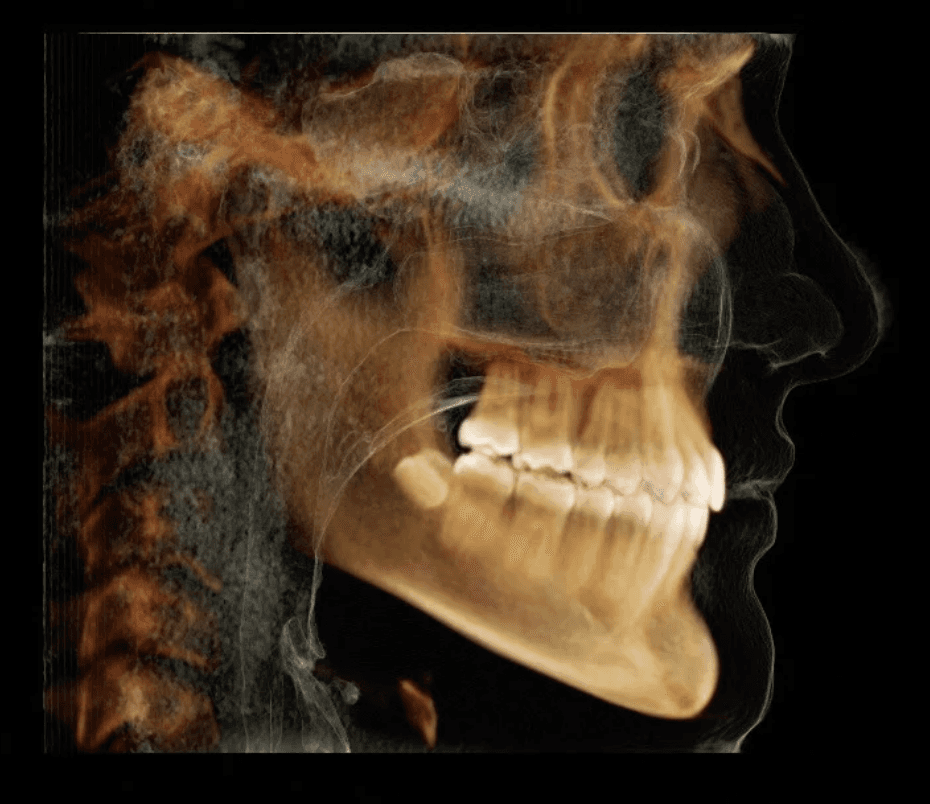

Initial treatment

X-RAYS